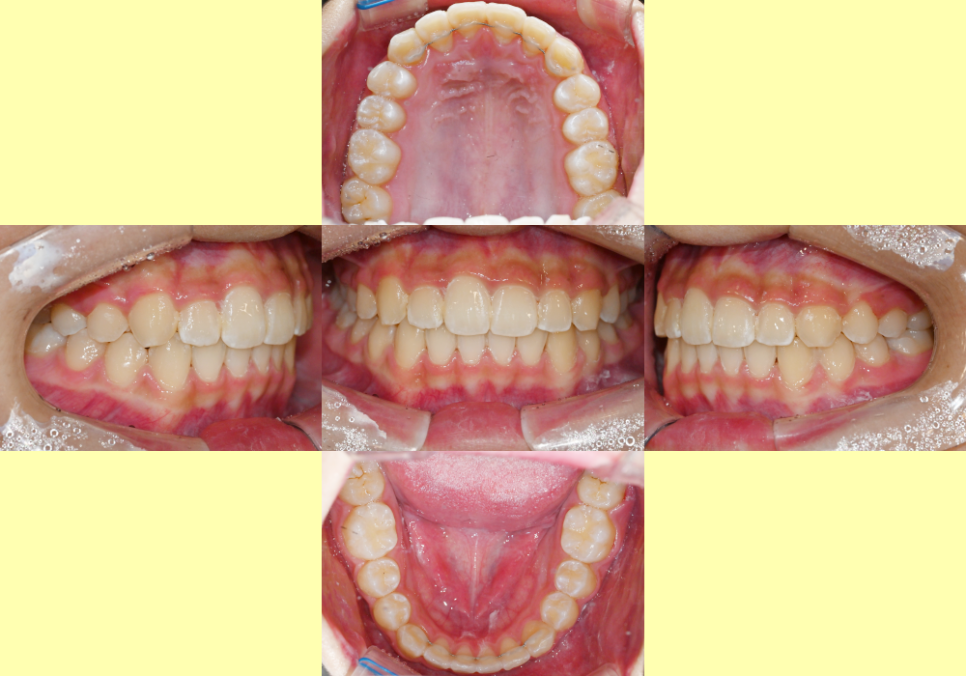

25.01.13

위아래 세부 조정을 진행한 뒤

모든 과정이 끝난 후에는

이렇게 가지런한 배열을 보실 수 있는데요.

앞니 틀어짐 및 비대칭으로 레벨이 달랐던 부분들도

가지런한 형태로 잘 개선된 형태를 볼 수 있습니다.

이번 사례를 통해

과개교합, 옥니, 덧니가 동시에

나타나는 복합 부정교합도

비발치 교정을 활용하여 개선할 수 있음을

알 수 있습니다.

치료기간 : 23.07.27 ~25.01.13